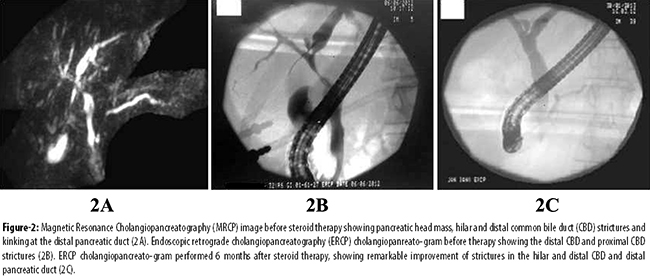

A 32-year-old male with history of asthma since childhood presented to our clinicin May 2012 with jaundice, epigastric pain andweight loss of 15kg over the preceding one year. General physical examination showed a protuberant left eye, which,according to the patient, was present for 12 years. Abdominal examination showed mild upper abdominal tenderness. He had sought prior medical consultation at another hospital where a computed tomography (CT) scan of abdomen was performed which revealed a dilated common bile duct (CBD), intra-hepatic duct (IHD)dilatation and a mass in the pancreatic head. Endoscopic retrograde cholangio-pancreatography (ERCP), performed about 10 months earlier, showed a distal CBD stricture for which a biliary stent was placed. The bilirubin levels had gradually decreased thereafter over a period of six months. A magnetic resonance cholangiopancreatography (MRCP) performed in our centre at the time of presentation, redemonstrated the pancreatic head mass measuring 2.2cm x 2.1cm, a distal CBD stricture and kinking of the distal pancreatic duct. Laboratory investigations showed a normal complete blood count (CBC) and deranged liver function tests (LFTs) with total bilirubinof 0.41 mg/dl, direct bilirubin 0.20mg/dl, alkaline phosphatase 774 U/L, gamma glutamyltranspeptidase 346 U/L, aspartate aminotransferase (AST) 56 U/L and alanine aminotransferase (ALT) 51U/L. ERCP was then performed for cholestatic LFTs. The previously placed plastic stent was removed, and the cholangiogramobtained showed an irregular CBD with two strictures, one in distal CBD and another in the proximal portion which extended into the right IHD. Two stents were placed, one each in the left and right ductal systems. Esophagogastroduodenoscopy and colonoscopy showed normal mucosa and histopathology revealed normal duodenal and colonic biopsies. Serological workup showed an elevated IgG value of 48.3G/L (reference range: 7.2-15.8 gm/L) with IgG4 level of 7.5 gm/L(reference range: 0.1-1.3gm/L). The level of CA 19-9 was normal i.e. 8.93 U/ml (routine: <33U/ml). The anti-nuclear antibody was weakly positive at a titer of 1:40, while the anti-smooth muscle antibody, anti-mitochondrial antibody and anti-liver kidney microsomal antibody were all negative. The viral serology, including hepatitis B surface antigen (HBsAg) and anti-hepatitis C antibodies (anti-HCV)were non-reactive. Liver biopsy showed minimally expanded portal tracts with lymphocytic infiltrate, fibrosis, occasional foci of lobulitis, mild focal cholestasis and no piecemeal necrosis. The modified histology activity index (HAI) stage was 2/6. The thyroid function tests were all normal but anti-thyroid peroxidase antibody level was found to be abnormally high i.e. 90.2 IU/ml (cut off <35 IU/ml). Thyroid scan showed normal uptake of radiocontrast. Anti-neutrophil cytoplasmic antibodies (ANCA), includingc-ANCA and p-ANCA, were negative. Magnetic resonance imaging (MRI) of the orbit showed thickening of all left-sided extra-ocular muscles, predominantly left lateral rectus and inferior rectus muscles with mild retro-orbital inflammatory changes and mild proptosis, consistent with orbital inflammatory pseudotumour (Figure-1).

Management was started subsequently with prednisone at a dose of 1 mg/kg/day, azathioprine 50 mg/day and ursodeoxycholic acid 250 mg thrice a day. Follow-up after 6 weeks showed improved LFTs. ERCP showed remarkable resolution of the strictures that were previously seen in the biliary tree (Figure-2).